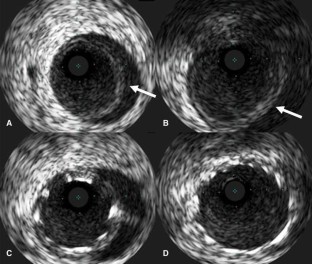

A 75-year-old female was admitted to our hospital with sudden back pain and right leg ischemia. Computed tomography showed acute type A aortic dissection with the occlusion of the right common iliac artery. The patient was treated with ascending aorta replacement and femoro-femoral bypass. Three hours after the operation, the patient went into a sudden shock. Electrocardiogram showed ventricular tachycardia and ventricular fibrillation. Percutaneous cardio-pulmonary support was administered and coronary arteriogram (CAG) was proceeded for evaluation of the coronary arteries. Although CAG revealed normal coronary arteries, intravascular ultrasound showed mobile intimal flap at left main coronary artery trunk, suggesting dissection of the coronary artery. Percutaneous coronary intervention of the left main coronary artery trunk was performed. The patient recovered from shock and was discharged from the hospital without any major complication.

Fig. 1